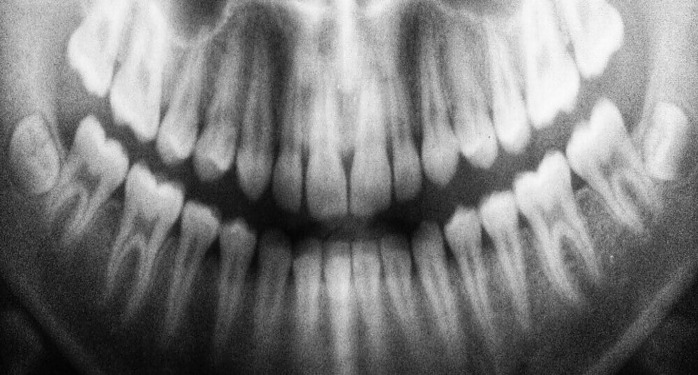

To gain a comprehensive understanding of a patient’s oral health, dental hygienists often use radiographic imaging techniques. X-rays help them visualize issues that may not be immediately apparent during a visual examination, such as cavities between teeth, bone loss, or abnormalities in tooth structure. This diagnostic tool enables dental hygienists to formulate effective treatment plans tailored to each patient’s specific needs.